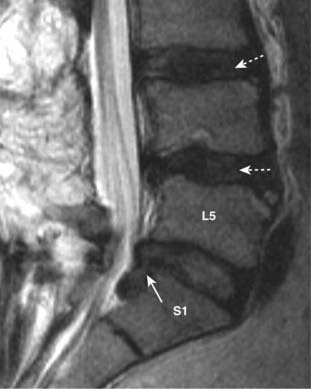

Figure 24-6 Disk herniation, L5-S1.

Sagittal T2-weighted image of the lower lumbar spine demonstrates disk material (solid white arrow) beyond the confines of the L5-S1 intervertebral disk space representing a disk herniation extending inferiorly. Notice that degeneration and desiccation of the other disks has led them to become darker than normal on this T2-weighted image (dotted white arrows).

imageThe majority of disk herniations occur at the lower three lumbar disk levels, L3-L4, L4-L5 (most common), and L5-S1. More than 60% of disk herniations occur posterolaterally, the location of the herniation determining the clinical presentation depending on which nerve roots are compressed.

image Disk herniations can be visualized on both CT and MRI. CT demonstrates disk material compressing nerve roots or the thecal sac. On MRI, the herniated disk material is usually a focal, asymmetric protrusion of hypointense disk material that extends beyond the confines of the annulus fibrosus (Fig. 24-6).